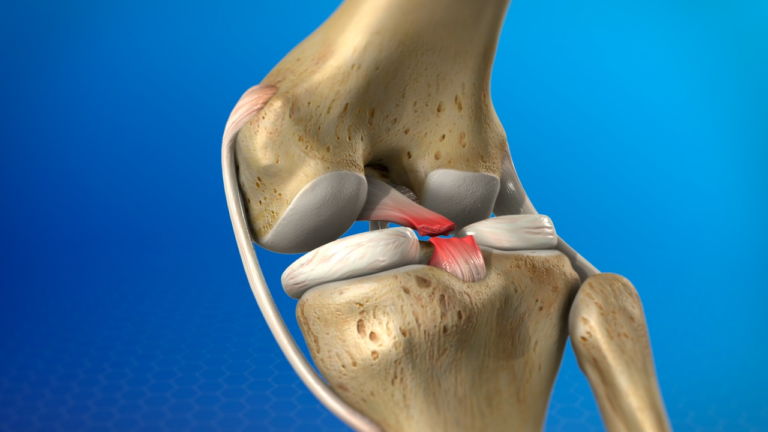

Knee osteoarthritis is a degenerative joint disease where the cartilage cushioning the bones of the knee joint breaks down over time. As the cartilage wears away, bones begin to rub against each other, causing pain, swelling, and joint stiffness.

- Previous knee injury (fractures, ligament injuries, meniscus tears)